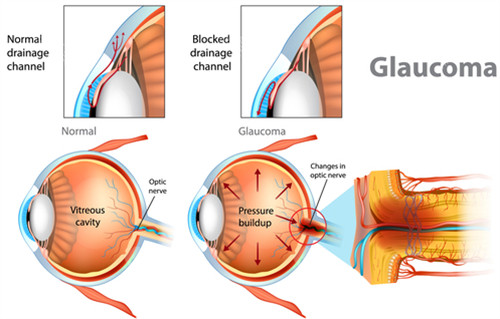

核心优势:由国内外比较有名眼科医师林顺潮医师创立,其发明的“激光虹膜边缘成形术”被纳入国内外青光眼诊疗指南。

前房穿刺术:针对急性青光眼眼压飙升,30秒内完成房水释放,快速缓解眼痛症状。

选择性激光小梁成形术(SLT):没有创口治疗早期青光眼,可重复操作,避免药物副作用。

个性化小梁切除术:根据角膜生物力学数据调整手术参数,术后散光发生率降低。

青光眼引流阀动态调节术:通过智能阀门控制房水流出量,避免术后眼压波动。